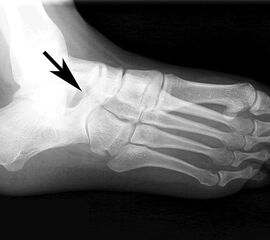

Röntgenbild (Fuß schräg) des Patienten aus Abb. 23 bis 26. Es zeigt sich eine Knochenbrücke zwischen Os naviculare und Calcaneus (Coalitio calcaneonavicularis).

Abbildung 27

Die Befunde aus Abb. 18 bis 21 deuten alle auf eine subtalare Coalitio hin die hier einen Spasmus der Peronealsehnen verursacht. Eine knöcherne Coalitio calcaneonaviculare läßt sich radiologisch meist auf der belasteten Schrägaufnahme des Fußes darstellen.